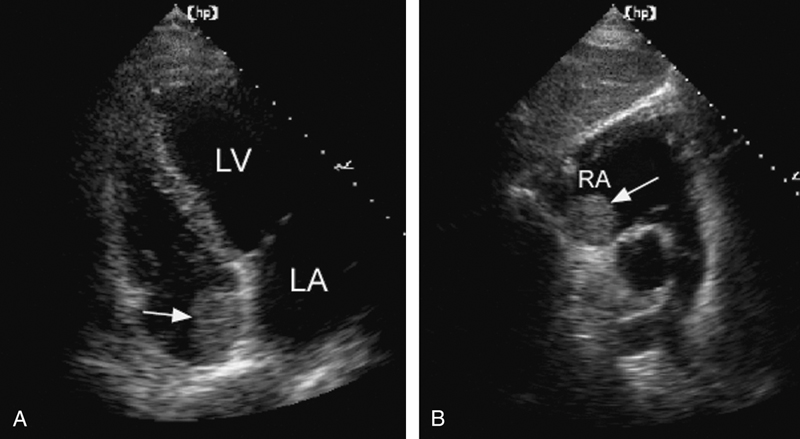

فحوصات تشخيصية لبعض امراض القلب والشرايين التاجية